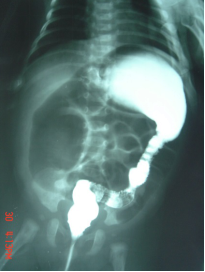

▷ 钡剂灌肠(Barium Enema)

- 无神经节细胞段与近端结肠口径差别、扩张段、狭窄段及移行段改变

- 结肠炎时粘膜锯齿状改变

- 24小时后钡剂滞留

操作简单,方法普及

新生儿确诊率80%

短段型不易诊断